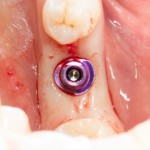

Ставший уже известным, начальный семинар по имплантологии, проводимый совместно с учебным центром «Симко» и крупнейшим производителем имплантов Dentsply Sirona Implants. За два с половиной года существования, он охватил несколько тысяч докторов в крупнейших российских городах, и вот теперь добрался и до Казани. Основы имплантологии преподаются на примере имплантационной системы Xive Dentsply Implants — и это отражено в названии семинара.

Это мой самый любимый и тщательно подготовленный проект — семинар по немедленной имплантации. Он уже дважды был в Москве, и однажды — в Нижнем Новгороде. На этот раз, мы проводим его совместно с компанией APEX в Санкт-Петербурге, и посвящен он будет… догадайтесь с трех раз?))) Через фокус немедленной имплантации будут рассмотрены различные имплантационные системы, операции остеопластики, синуслифтинга, удаления зубов и превентивной аугментации лунок.

Каждый день в нашей клинике GIC кто-то проходит Индивидуальное Практическое Обучение. Каждый день кто-то помогает на операциях, принимает участие в консультациях и послеоперационных осмотрах, решает те же клинические задачи, что и мы. Этим «кем-то» может быть любой из вас. Или, почти любой. В общем, мы делаем из людей имплантологов в условиях, максимально приближенных к боевым.